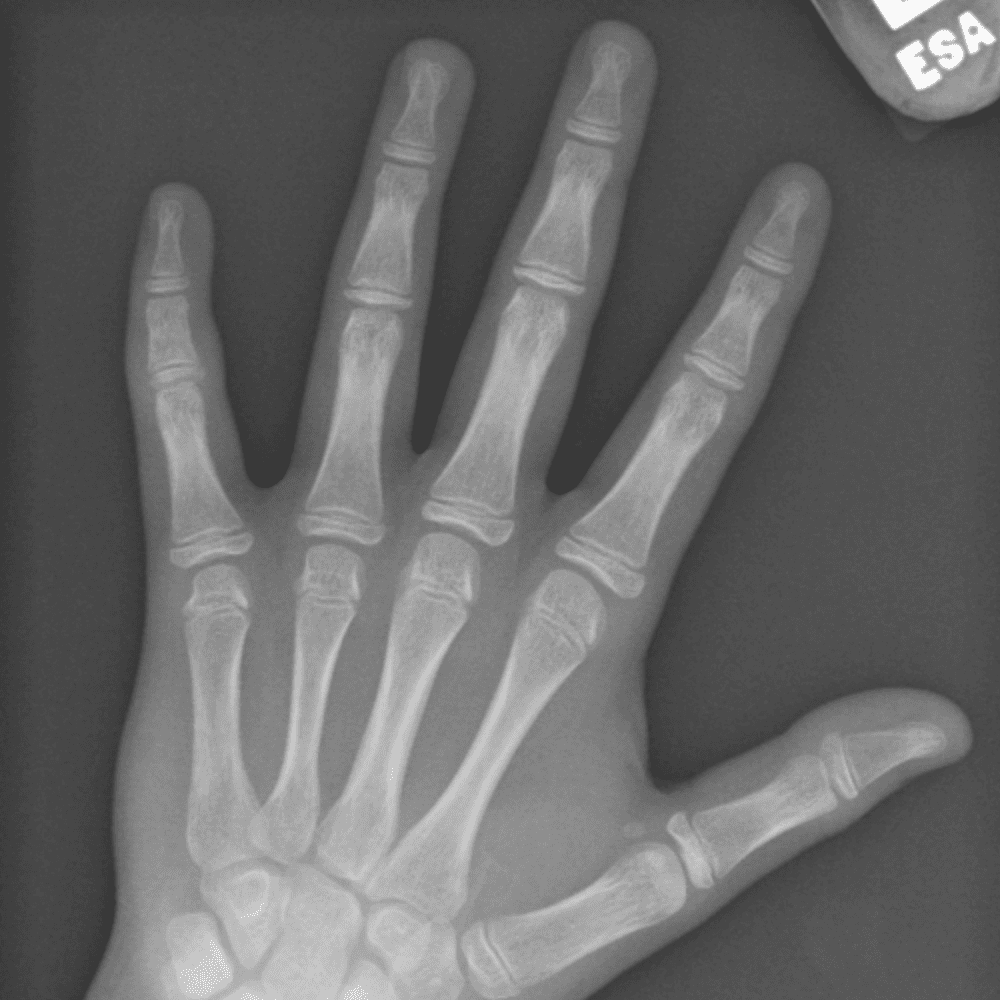

Simulates call by including subtle or difficult cases and some normals.

30 cases